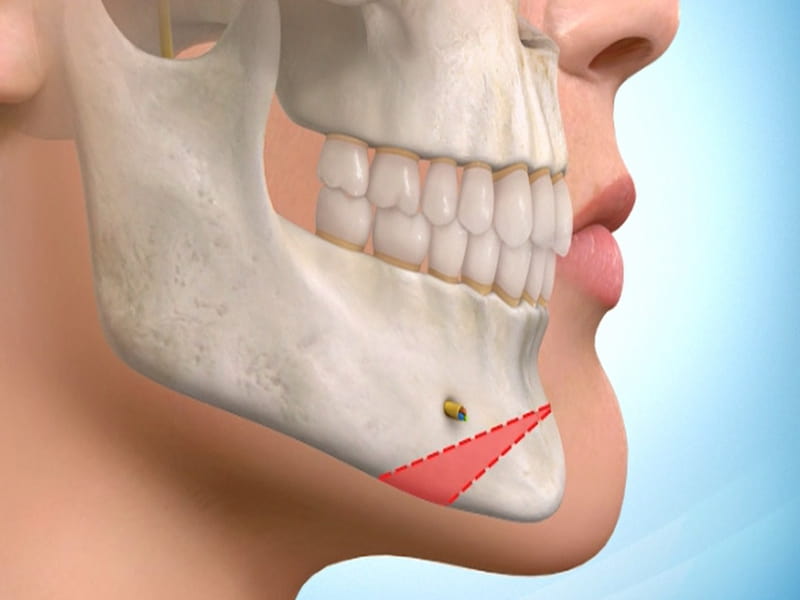

در این روش، ایمپلنت زیر لثه کاشته میشود و به فک متصل میشود.

سپس، برای اصلاح زاویه فک و تعامل بین فکها، از پروتکلهای درمانی خاصی استفاده میشود که شامل تنظیم فشار و قدرت ایمپلنت، استفاده از براکتها و وسایل جانبی دیگر است.

این ایمپلنت زیر لثه کاشته میشود و به فک متصل میشود.

باید قادر به تحمل فشار و نیروی زیادی باشد تا بتواند ناهنجاریهای فکی-دندانی را بهبود بخشد.